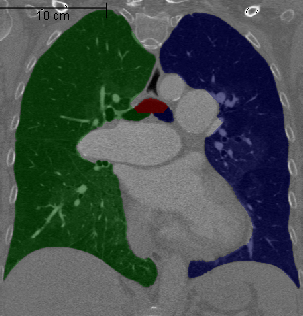

We found a correlation between DM and mPAP of (Spearman correlation coefficient, p<0.01). There was a significant difference between the DM of patients with and without PH (Table 2, p<0.05), thus enabling to discriminate the two groups on our dataset of 24 patients. Two representative vessel segmentation results of the PH study datasets are shown in Figure 7.